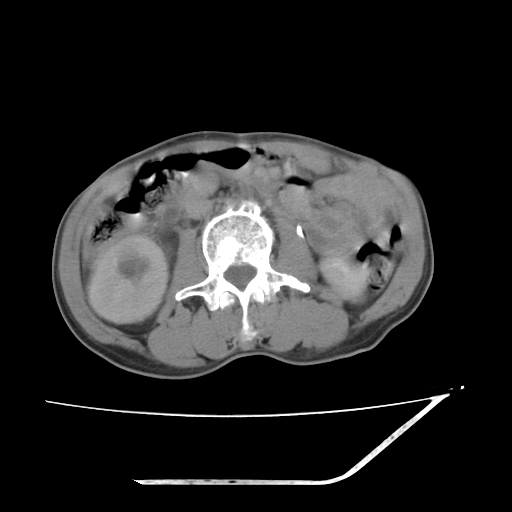

增强

考虑右肾盂癌,肾动脉受侵,右肾功能减退,右肾盂输尿管积水,管壁增厚,考虑种植转移,应该把下面扫完的

支持右侧肾盂癌伴肾静脉瘤栓形成可能性大,右肾结石.肝右叶后段低密度影,不除外转移.

右肾盂旁ca并肾静脉瘤栓形成/肾功能降低。

右肾盂癌,肾动脉受侵,右肾盂输尿管积水,管壁增厚,考虑种植转移

1.右侧肾盂癌伴肾盂积水。

2.肾脏功能减退,原因有:(1)肾动脉受侵。(2)肾静脉受侵(3)肾积水,等。本例,肾动脉显影较好,但受压明显;肾静脉无明显显示,受压或静脉癌栓,下腔静脉腔内未见明显充盈缺损。

3.右侧上段输尿管扩张,原因:(1)积水所致;(2)种植。